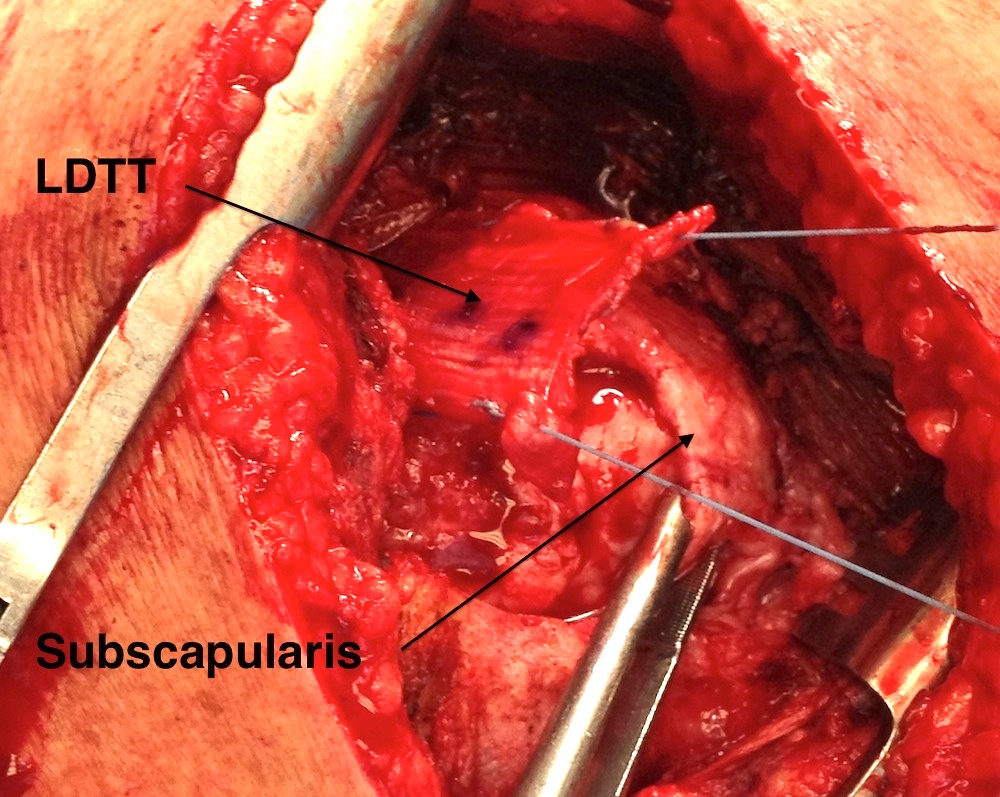

Identify LDTT muscle belly most lateral and follow up onto humerus

Follow tendon up onto the humeral insertion and release, suture tendon

Detach deltoid from lateral acromion +/- perform arthroscopically

- tunnel tendon under deltoid & acromion

- suture anchors repair to greater tuberosity +/- subscapularis

Identify posterior deltoid and tunnel tendon under posterior deltoid into subacromial space

Repair with suture anchors to greater tuberosity and to subscapularis